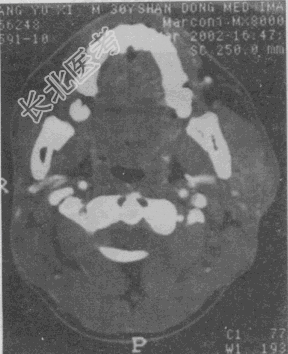

- 单项选择题女性,45岁。发现左侧腮部肿块1年余, 逐渐长大,无明显不适。CT检查如图所示, 应首先考虑

A、腮腺囊腺淋巴瘤

B、血管瘤

C、脂肪瘤

D、淋巴瘤

E、多形性腺瘤